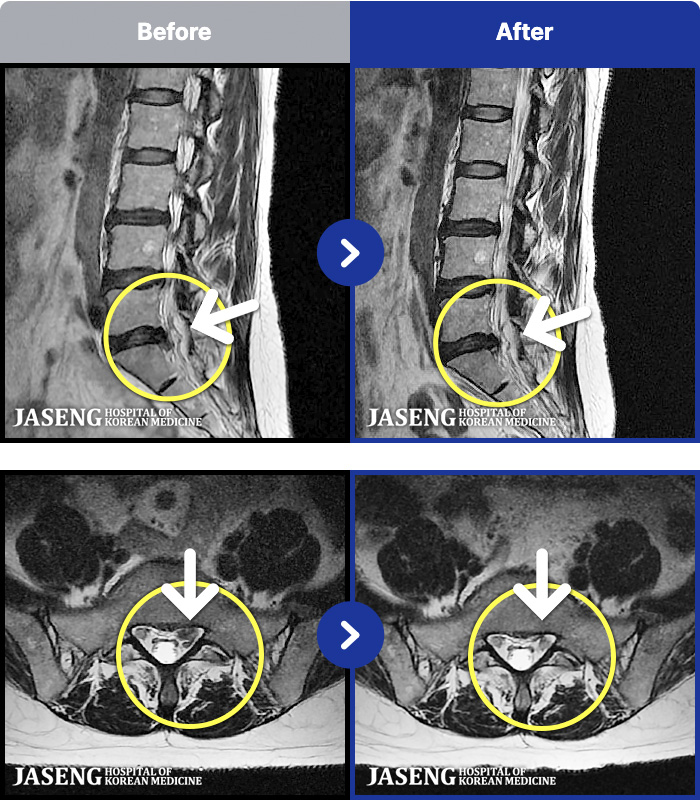

54 MRI ũ ʸ Ȯϼ.

[ϻ] 24.07.25~25.08.01